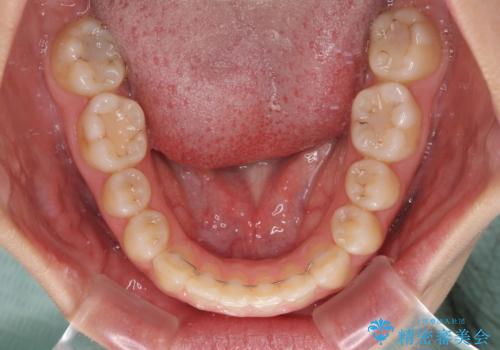

- 前歯の開咬と、上顎前歯の八重歯やデコボコを気にして来院された患者様です。

上顎歯列が狭窄していたため、急速拡大装置により上顎骨を側方に拡大し、その後ワイヤー装置にて矯正治療を行うこととしました。

上顎骨を拡大することで、八重歯やデコボコを歯列に収めることができ、下顎の歯が外に位置していた奥歯の咬み合わせも改善することができました。

スペースも短期間に獲得できるため、1年程度で治療を終えることができました。